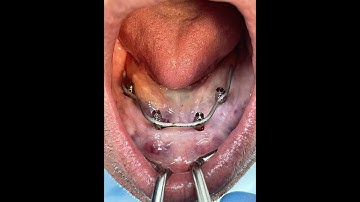

Intra oral Welding Titanium Frame, immediate loading